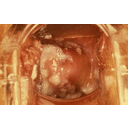

Tricomoniasis eritema macular.jpg

Vaginosis Bacteriana flujo.jpg